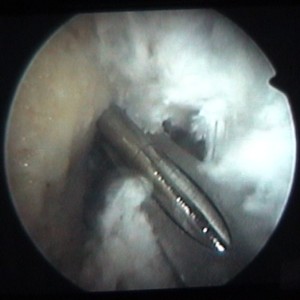

enlèvement d'un ménisque |